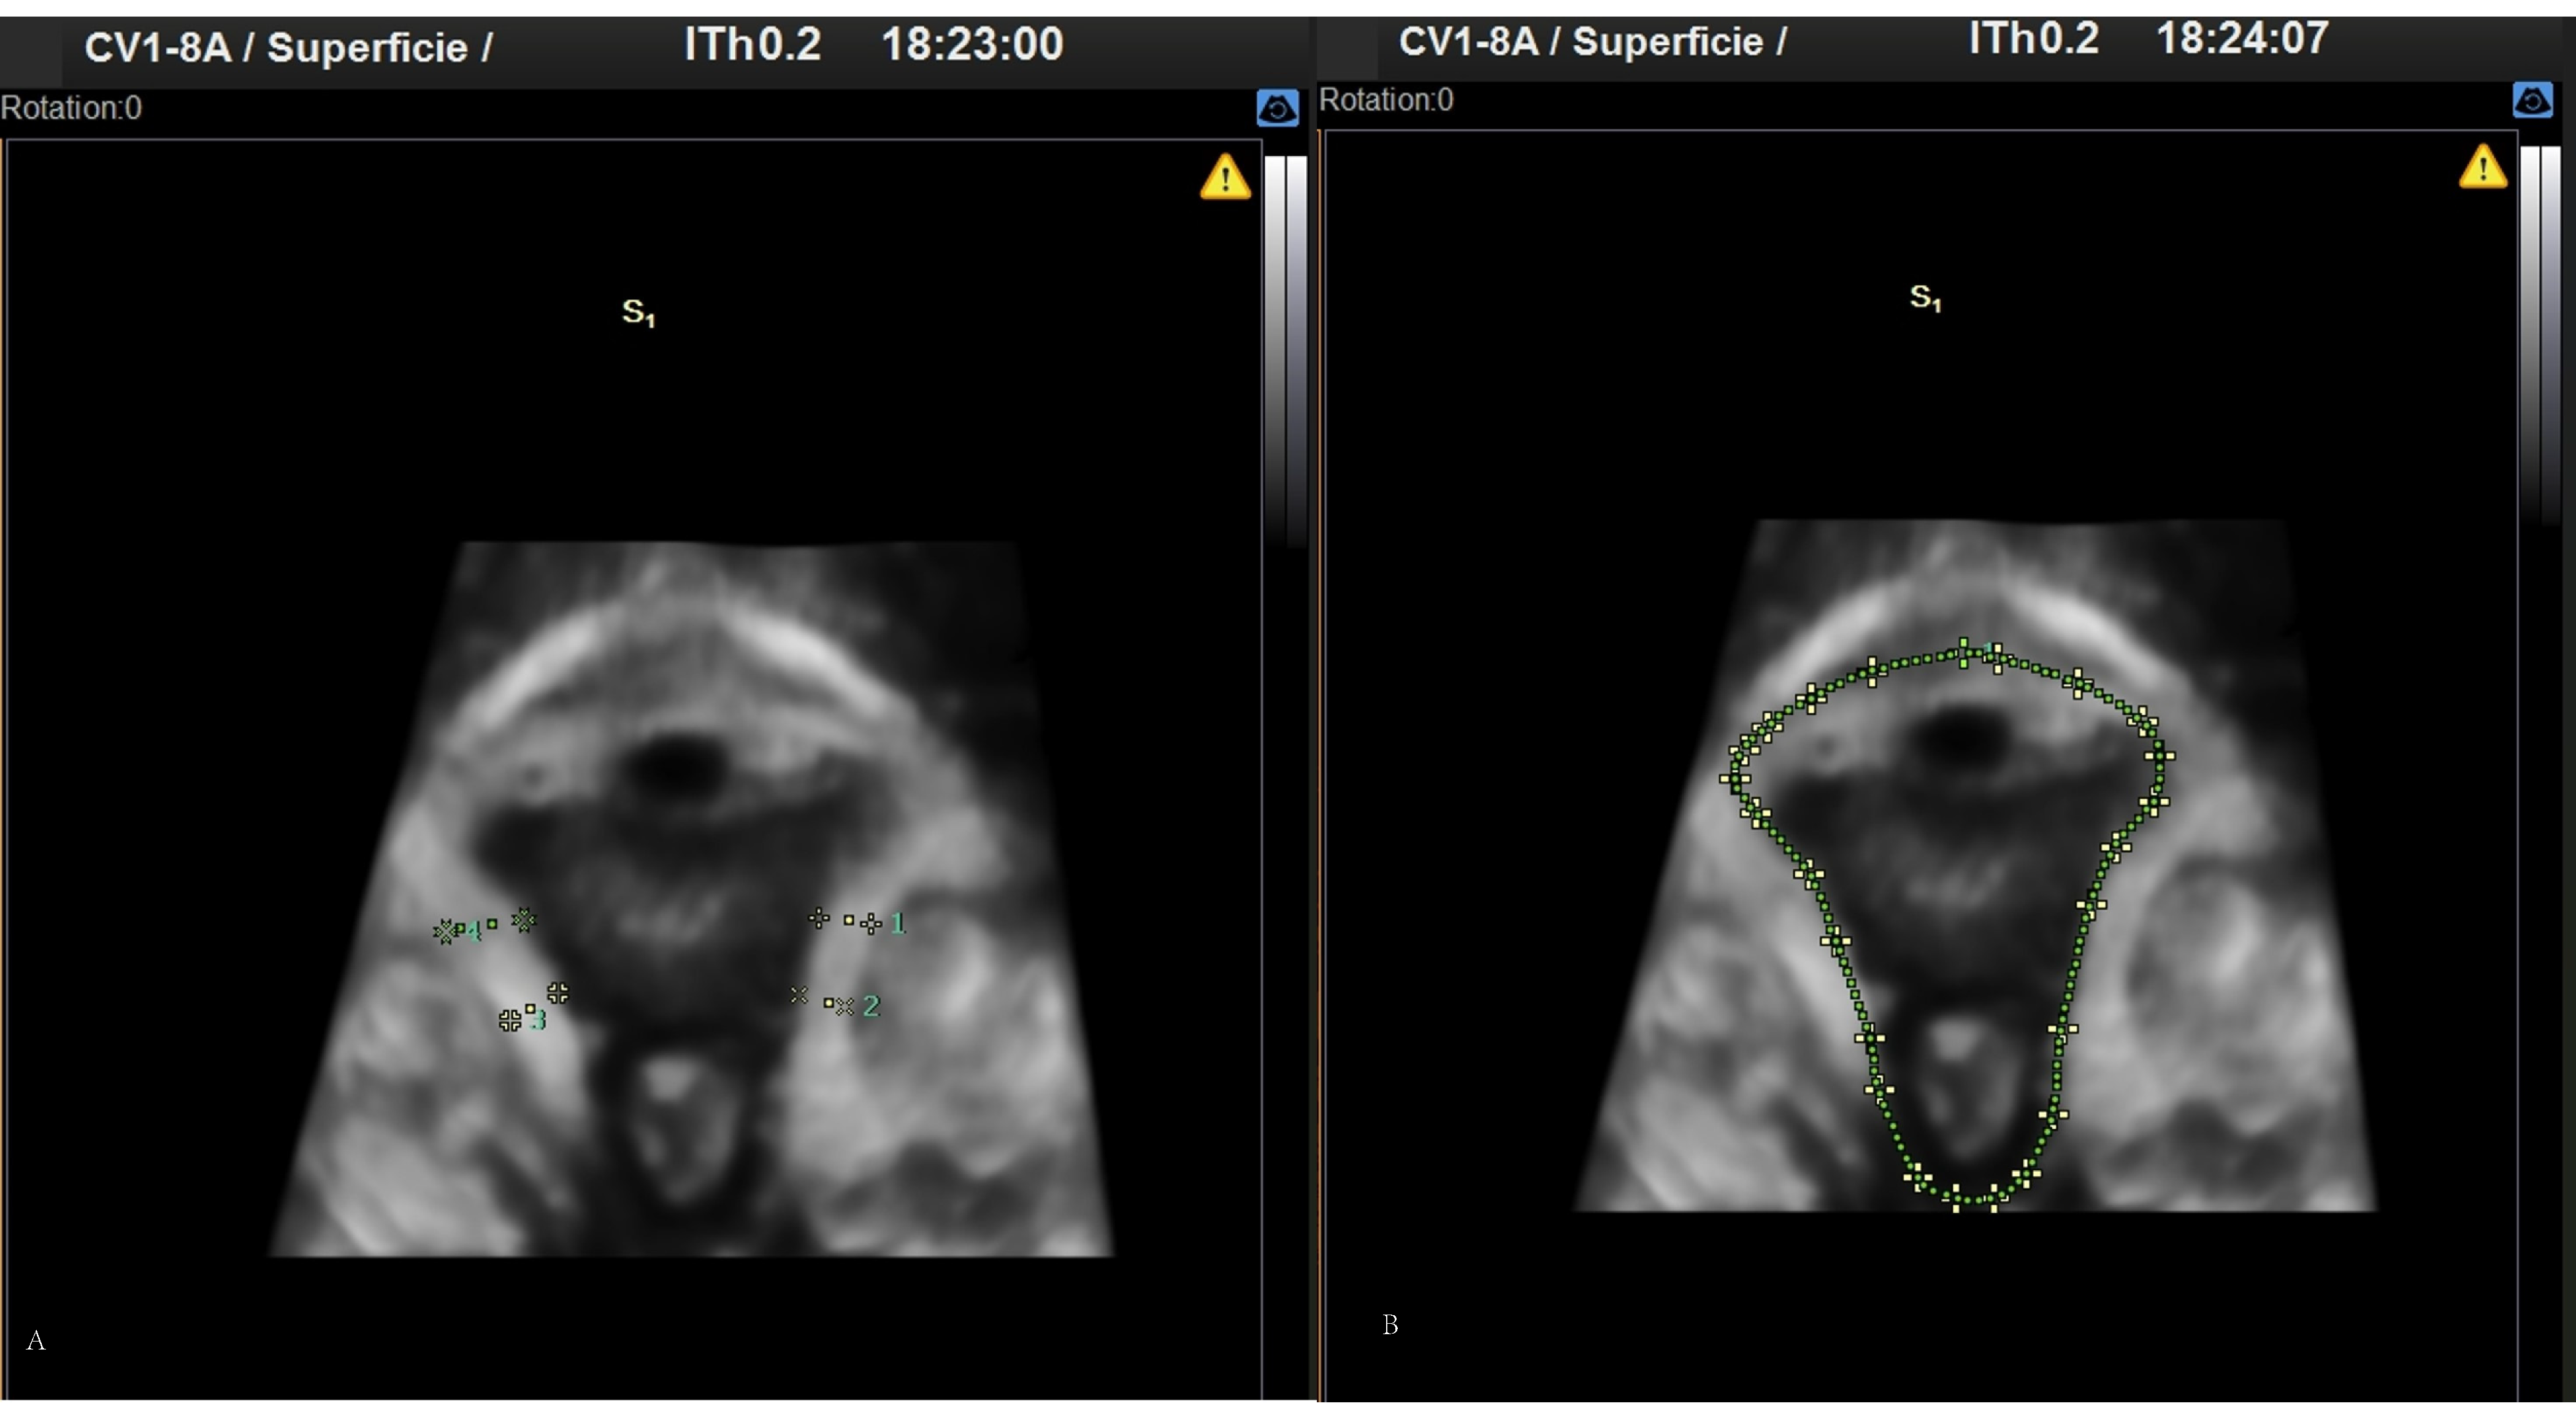

2. Materials and Methods